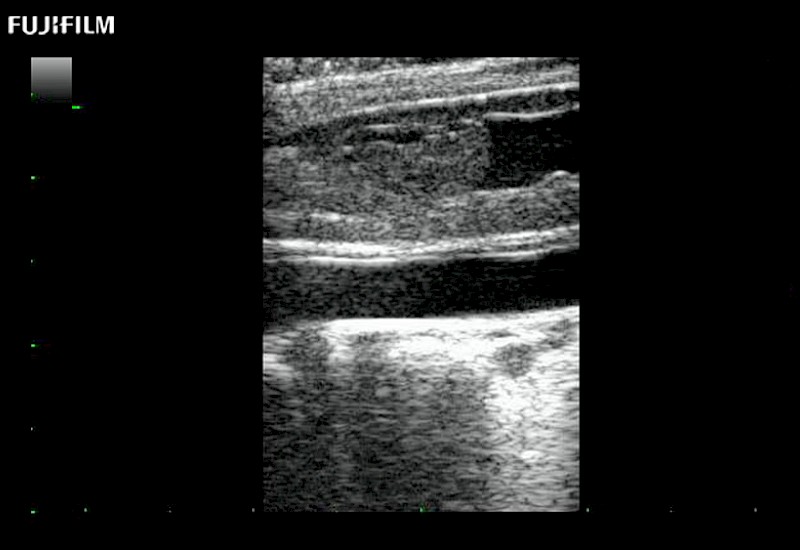

Hockey-stick linear array transducer is the transducer of choice for cervical spine scanning.

Main Specifications: